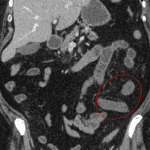

- Thrombus in the mid and distal SMA extending into proximal jejunal branches

- Mild luminal distension and wall hypoenhancement of an approximately 20 cm segment of jejunum in the left mid abdomen

- Acute mesenteric ischemia due to arterial occlusion

Thrombus in the mid and distal SMA extending into proximal jejunal branches which may represent in situ thrombus versus thromboembolism. Mild distension and wall hypoenhancement of an approximately 20 cm segment of jejunum in the left mid abdomen is concerning for developing bowel ischemia. No pneumatosis, portal venous gas, or pneumoperitoneum.